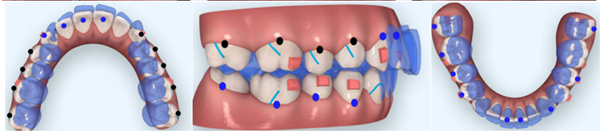

La necesidad cada vez mayor de obtener un camuflaje estable y sin efectos secundarios a nivel dentoalveolar ha permitido implementar nuevas técnicas de anclaje absoluto mediante minitornillos, como una alternativa temporal, utilizada para la retracción del sector anterior sin pérdida de anclaje en el sector posterior cuando existen extracciones dentales, la intrusión molar permitiendo la rotación mandibular en sentido antihorario, la intrusión del sector anterior en casos de un crecimiento vertical excesivo del maxilar, y la implementación de alineadores invisibles más ligas intermaxilares de Clase II de manera combinada.

Camuflaje con extracción de primeros premolares superiores y minitornillos interradiculares.

En esta técnica inicialmente se deben realizar las extracciones de los primeros premolares superiores junto con la inserción de minitornillo en la misma cita, el mismo debe ser de tipo autoperforante (1,4 mm de diámetro y 8 mm de longitud) colocándolo entre las raíces del primer molar superior y el segundo premolar de forma bilateral. Los minitornillos se cargan inmediatamente con una cadena elastomérica para la retracción del canino hacia una Clase I, posterior a esto se coloca resortes helicoidales cerrados de níquel-titanio (NiTi) que van desde un bucle elaborado en el arco de acero 0.017x0.025 pulgadas o desde un hook crimpable en el arco del mismo calibre (figura 2 y 3), con una fuerza de 150 gr con el vector de fuerza pasando por arriba del centro de resistencia de tal manera que los dientes antero superiores se retraigan de manera simultánea hacia arriba y atrás, las fuerzas aplicadas se repiten cada veintiún días permitiendo el cierre de espacio de las extracciones 14.

Figura 2. Cierre de espacio de las extracciones.

Elaboración: Los autores.

Figura 3. Cierre de espacio y tracción anterior.

Elaboración: Los autores.

Camuflaje con extracción de primeros premolares superiores y retracción en masa del bucle en T.

Para esta técnica se realiza la extracción de los primeros premolares superiores con una retracción en masa directamente de los 6 dientes anteriores mediante un retractor canino en T (figura 4), activando gradualmente cada mes de 1-2 mm para el cierre del espacio del diente extraído, consiguiendo una Clase I canina y Clase II molar, debido a que es una técnica con anclaje recíproco 15.

Figura 4. Tracción sector anterior con bucle.

Elaboración: Los autores.

Camuflaje con extracción de cuatro segundos premolares superiores e inferiores y minitornillos infracigomático más elásticos de clase II.

Esta técnica consiste en mejorar el perfil convexo y el sobrecrecimiento vertical con control sagital y vertical de la dentición, utilizando anclaje absoluto mediante minitornillos infracigomático (diámetro, 1,6 mm; longitud, 11 m) y también para la retracción e intrusión de los dientes anteriores, además de utilizar minitornillos a nivel mandibular para distalizar (Figura 5).

Figura 5. Cierre de espacios mini tornillos infracigomáticos.

Elaboración: Los autores.

Camuflaje con alineadores transparentes (invisalign)

La fase I fue diseñada para la descompensación en cuanto a la inclinación de los dientes anteriores superiores e inferiores y la intrusión de los dientes posteriores permitiendo la proyección mandibular hacia adelante ya sea por extracción de premolares, los alineadores invisibles producen resultados que son clínicamente aceptados y podrían ser comparables con la aparatología fija, con inclinaciones leves o moderadas y la fase II fue planificada para corregir la maloclusión dental y esqueletal de Clase II 15.

El plan de tratamiento digital inicial ClinCheck ® incluye la descompensación de los incisivos superiores e inferiores a través de la proinclinación de los incisivos superiores utilizando crestas eléctricas. Se realiza la intrusión de los molares y premolares superiores para permitir la rotación mandibular en sentido antihorario, en el arco inferior hay intrusión de incisivos inferiores además de la intrusión de molares y premolares inferiores, estos alineadores incluyen cortes para elásticos de Clase II y Clase III, además de poder realizar la expansión del arco superior para mejorar el posicionamiento hacia delante de la arcada inferior, además la expansión de la arcada inferior proporciona espacio para mover los incisivos inferiores hacia lingual 15.

Figura 6. Planificación digital.

Elaboración: Los autores.